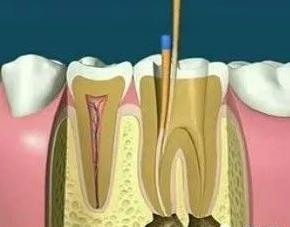

根管治疗,也称为牙髓治疗,是治疗牙髓疾病和根尖周疾病的有效方法。通过去除根管中的炎性牙髓和坏死物质并进行适当的消毒,填充根管以消除根管内容物对根尖周围组织的不利刺激,防止根尖周病变的发生或促进根尖周愈合病变。此操作可保护牙齿,因此可与拔牙互补。根管治疗很麻烦,通常需要2-4次就诊才能完成,并且患者会遭受更多的痛苦。

1、术前拍摄X线片:在根管治疗过程中,在根管治疗术前拍X线片,可以帮助诊断,了解髓室的位置和根管数目及形态,测量根管工作长度。

2、揭开髓腔:去净腐质和原有充填物、揭净髓顶,看到整个髓底解剖结构以便后续治疗顺利进行。

3、确定根管工作长度:应用平行投照X线方法、根管长度测量仪确定根管度,最好插针拍X片。

4、根管预备:根管清理成形的目的是去净根管壁上的感染物,通过根管器械的切削作用去除感染的牙本质并清理根管壁细菌以利于根管充填。

5、根管冲洗、消毒:根管冲洗的目的是清除微生物、冲掉残渣,润滑根管器械和溶解有机残渣。然后,再进行根管消毒,使根管内达到无菌状态。

6、根管充填:封闭整个根管系统、堵塞主根管和侧副根管出口、防止微生物和液体的渗漏。无论是侧方加压法还是垂直加压法,应做到根管充填致密,根管充填后X线片上无根管腔隙,也不能超出根尖孔。